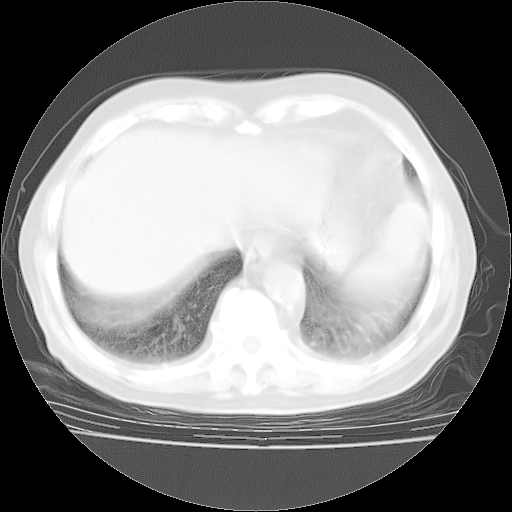

今天部分检查

轻微咳嗽,无痰,(体温正常时)R20次/分,P75次/分,双肺底、腋下可闻及少量捻发音。下肢轻度浮肿。

血常规:白细胞9.11×109/L,N0.92,L5.64,血小板39.2×109/L,HB148g/L,ESR2mm/H。

尿常规:潜血+

血生化:总蛋白69.71g/L,白蛋白38.40g/L,球蛋白31.31g/L,CRP27.9mg/L,尿素氮11.98mmol/L,肌酐106μmol/L,乳酸脱氢酶1099 U/L,肌酸激酶108U/L,CK-MB 61U/L。

腹部B超:胆囊壁增厚,肝、胆、胰、脾、肾无异常,肠系膜淋巴结、腹膜后淋巴结无增大。

ECG:右心室增大

心脏超声检查:无右心室增大。

增加治疗:异烟肼、利福平、乙胺丁醇,静滴左氧氟沙星、参麦注射液。甲强龙从80mg暂减为40mg。

强的松3月1日改为10mg qd,4月1日改为10mg qod。3月份以前的减量过程和环磷酰胺疗程需等明天查看记录(我岳父自己做的记录在他家里)。